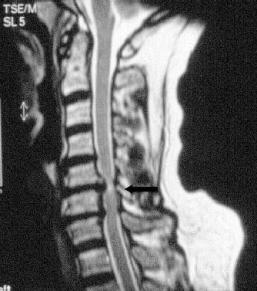

Synonyme: MRT, Magnet-Resonanz-Tomographie, "große Röhre"

Diagnostische Technik zur Darstellung der inneren Organe und Gewebe mit Hilfe von Magnetfeldern. Röntgenstrahlen kommen nicht zum Einsatz. Besonders geeignet ist die Technik zur Darstellung von Nerven- und Bandscheibengeweben. Damit ist sie die bevorzugte Untersuchung bei Wirbelsäulenerkrankungen.

Die MRT beruht nicht auf Röntgentechnik, sondern benutzt das unterschiedliche Rotationsverhalten von Atomen in einem Magnetfeld als Prinzip zur Bildherstellung.

Unterschiedliche Gewebe können mit sehr hoher Detailerkennbarkeit dargestellt werden.

Wichtig: Teilen Sie dem Arzt mit, ob sich Metallteile oder Schrittmacher in Ihrem Körper befinden und ob Sie unter Platzangst leiden.